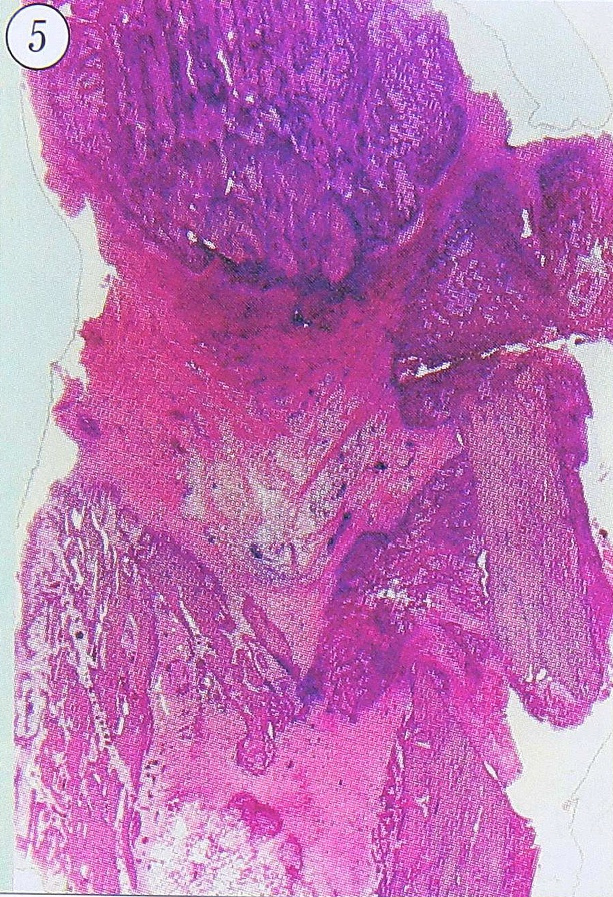

Рис. 5. Хронический травматический остеомиелит с продуктивным воспалением низкой активности в межотломковой фиброзной ткани. Бедренная кость больного. Ув. 8.

В некоторых случаях хронического ТО костные отломки были сращены фиброзной или фиброзно-хрящевой тканью неоднородной толщины, структуры и степени зрелости, в которой определялись участки отека и миксоматоза, очаговые лимфоцитарно-макрофагально-плазмоцитарные инфильтраты (фиброзирующая форма хронического ТО — рис. 5), иногда — округлые или щелевидные хронические микроабсцессы. При этом костные регенераты, являющиеся одновремено элементами костной оболочки остеомиелитического очага, были построены из незрелой костной ткани и подвергались перестройке, изредка — патологическим переломам. Подобные гистологические изменения соответствуют картине «инфицированного ложного сустава», к тому же морфогенетически они всегда являются производными ТО [6, 16].